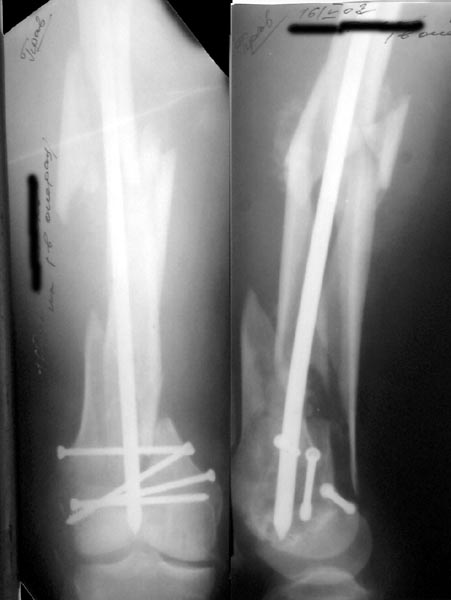

See attached case that was done several years ago before LISS. He had comminuted trochlea and anterior blocking screws were used to prevent anterior IMN cut-out.

Да, примерно так и сделали. Надо было, пожалуй, кончик гвоздя еще спилить, чтобы отверстие было еще дистальнее. Англоязычные коллеги еще

советовали винты в передне-заднем направлении вводить, но что-то не увидел, где там подходящее место.

Since it was done closed the shaft will heal or at worst need an exchange IMN.

Nice job.

Мы пошли на операцию с планом попытаться сделать закрытый интрамедулярный, а не получится - сделать аппаратом. Посчитали, что получилось, хотя на еженедельной конференции ожидаются некоторые проблемы с объяснениями ;-)

Насчет стабильности для ранней нагрузки, конечно, сомнительно, но при таком повреждении ранняя нагрузка противопоказана в любом случае. Для ранних движений Должно хватить. Снимки в следующем сообщении.